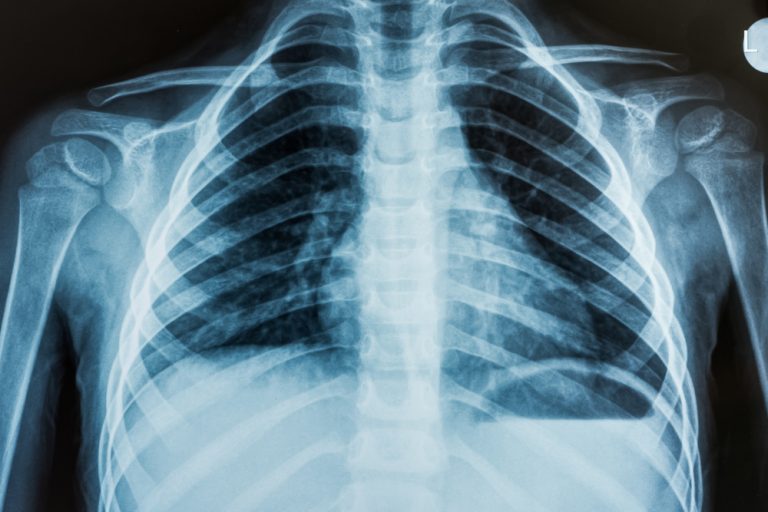

- Рентгенография легких.

- Будет выполнен рентген, который поможет установить, какой орган стал причиной легочного кровотечения.

После первичной оценки, может потребоваться проведение дополнительных исследований, таких как рентгенография грудной клетки или компьютерная томография (КТ), для выявления источника кровотечения. В этом процессе активно участвуют радиологи, которые помогают интерпретировать результаты изображений и могут предложить минимально инвазивные процедуры, такие как бронхоскопия, для визуализации дыхательных путей и остановки кровотечения.